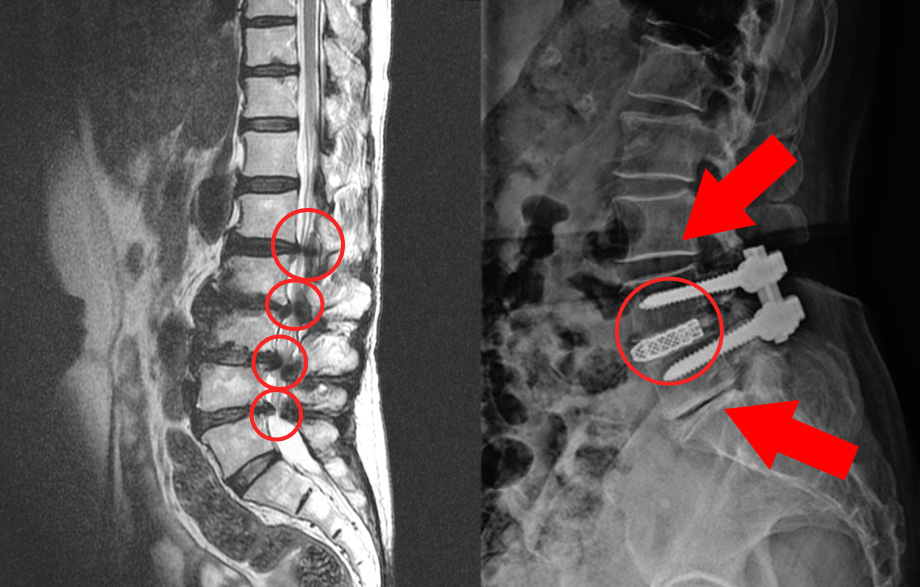

그런데, 보시면 협착증은 이 부분만이 아니라 주변 부분도 다 퇴행되어 있습니다. 그래서 고정술을 한 이후에 이 부분이 구부리지도 펴지도 못하게 되기 때문에 이미 퇴행된 주변 마디에 부담을 주게 됩니다. 주변 마디가 더 많이 구부렸다 폈다가 해줘야 하는 것이죠. 그런데 앞서 말했듯이 협착증 환자는 이미 주변 위아래 마디도 퇴행되어 약해진 상태인데, 추가적으로 부담을 주니까 시간이 흐르면 주변 부위도 문제가 생기게 되는데요. 이것을 인접분절질환이라고 합니다. 일반적으로 척추유합술 후 이러한 문제가 많이 발생하기 때문에 인접분절질환이라는 이름까지 만들어져 있습니다. 이러한 인접분절질환은 특히 수술 후 관리를 잘 못하면 당연히 더 잘 생기기 때문에 유합술을 했다면, 이 인접분절질환이 생기지 않도록 관리를 세심하게 잘 해줘야 합니다.

척추협착증 수술에 많이 하는 척추유합술, 유합술 후 발생하는 인접분절질환에 대해 꼭 알아야 합니다